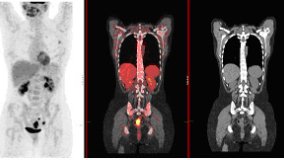

Clinical PET/CT

Establishing a clinical protocolClinical applicationsArtefacts and normal variantsClinical Imaging